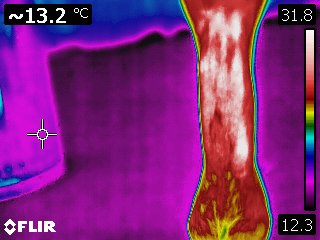

Infrared thermography is a dynamic modality providing a detailed, real-time image of the physiology of an area. It also provides an evaluation of the intensity and distribution of the heat associated with a tendon or ligament. As such, it is a method for specifically and repeatedly monitoring the extent of initial damage and to follow the repair process. Because thermography can accurately and repeatedly differentiate between various areas of tendon within a larger damaged area, sequential scans can provide useful information for treatment and in the repair process, as well.

Courtesy Kenneth Marcella, DVM

Courtesy Kenneth Marcella, DVM

Courtesy Kenneth Marcella, DVM